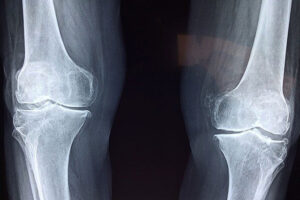

Arthritis Treatment गठिया के घरेलू उपचार

आज कल हमारी दिनचर्या हमारे खान -पान से गठिया(Arthritis Treatment) का रोग 45 -50 वर्ष के बाद बहुत से …